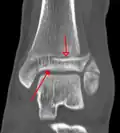

Fracture of both sides of the ankle with dislocation as seen on anteroposterior X-ray. (1) fibula, (2) tibia, (arrow) medial malleolus, (arrowhead) lateral malleolus

On X-rays, there can be a fracture of the medial malleolus, the lateral malleolus, and/or of the anterior/posterior margin of the distal tibia. The posterior margin (known as the posterior malleolus) is much more frequently injured than the anterior aspect of the distal tibia. If both the lateral and medial malleoli are broken, this is called a bimalleolar fracture (some of them are called Pott's fractures). If the posterior malleolus is also fractured, this is called a trimalleolar fracture.

CT scans may be indicated when there is concern for a highly comminuted fracture or a fracture involving the joint surface.[10] This imaging may be used for surgical planning.